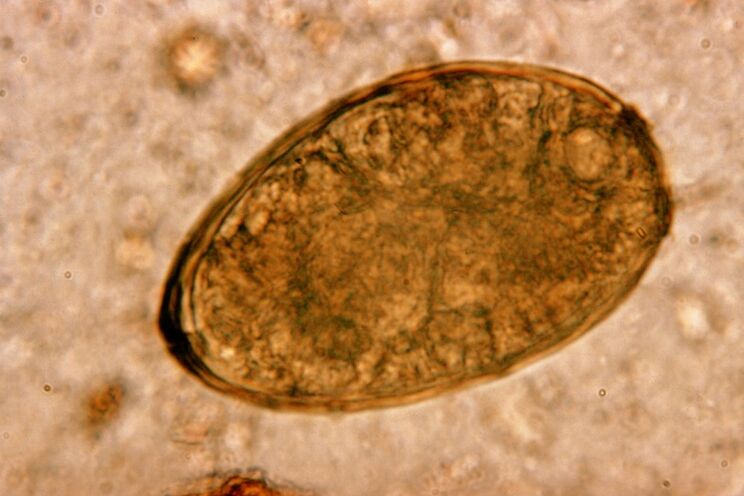

Il trematode vive in coppia nei polmoni e forma cisti nei bronchi. L'infestazione avviene quando si consumano granchi e gamberi infettati dal parassita. Nel tratto gastrointestinale, il trematode polmonare penetra nel peritoneo ed entra nei polmoni attraverso il diaframma, provocando la tosse persistente del paziente.

Il trematode polmonare dei piccoli vermi, che appartiene alla classe dei trematodi, è “specializzato” nel parassitare specificamente i polmoni. Causa problemi molto più gravi al sistema respiratorio rispetto, ad esempio, ai nematodi.

Nel sito di localizzazione si verificano infiltrati ed emorragie, creando cavità piene di metaboliti in decomposizione di vermi, parassiti morti e tessuto polmonare. Il danno causato dal trematode polmonare è aggravato dal fatto che si tratta di un fegato lungo che può vivere nel corpo dell'ospite fino a 20 anni.